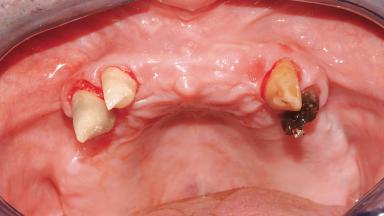

A 61-year-old male patient with a failing fixed maxillary rehabilitation and a fixed mandibular rehabilitation requested a new fixed maxillary rehabilitation. The patient was wearing a temporary metal-reinforced maxillary bridge inserted two years before the consultation. He reported that his previous dentist did not want to insert a definitive framework because he considered the residual teeth to have a negative prognosis. The patient reported a history of recurrent caries and endodontic complications as the main reason for the previous extractions. The anamnesis was negative for periodontal disease and bruxism. The patient’s chief compliant was the mobility of his maxillary prosthesis, which needed to be re-cemented frequently, and discomfort during chewing.Moreover, the patient was not satisfied with the esthetic appearance of his maxillary teeth, which he found too long. The patient asked for a stable and comfortable fixed maxillary rehabilitation and firmly rejected any removable solution.